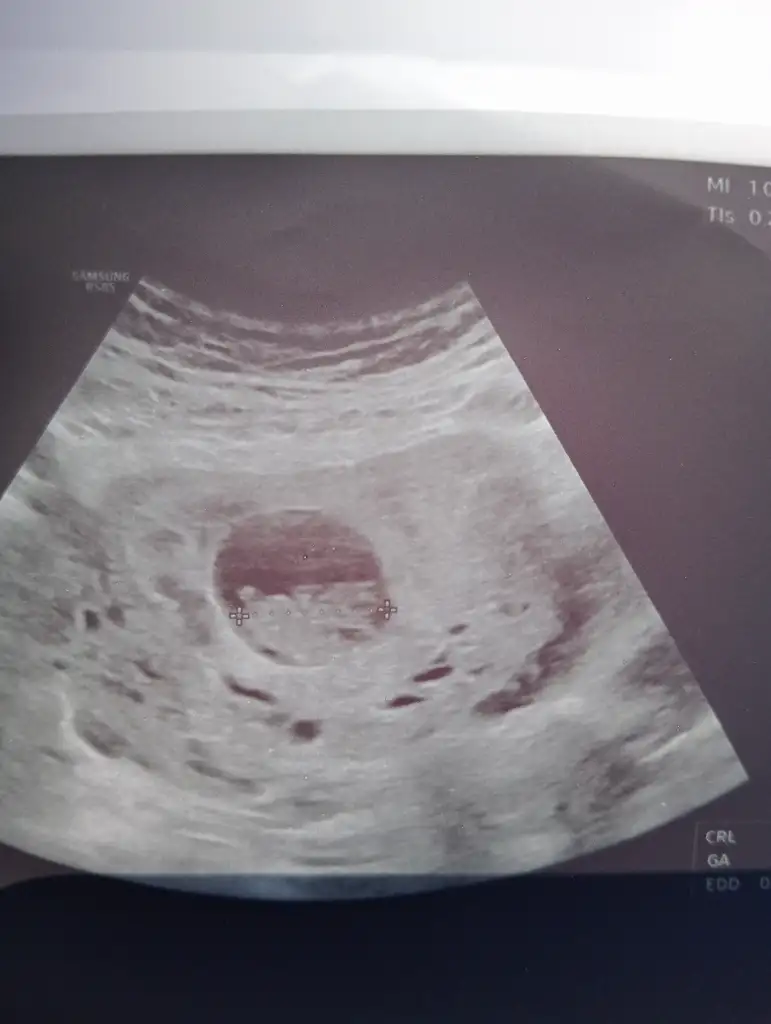

Banada bakar mısınız 8 haftalık

Benim miniğimi de tahmin edebilecek teyzeleri var mı 8 haftalık şimdiden teşekkür ederim